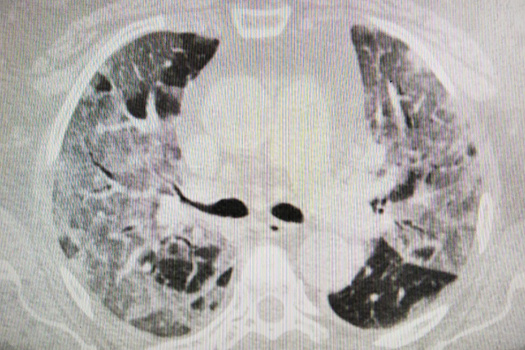

There are now more than 200 people in the hospital’s infectious disease ward. Some of them are being discharged, but new patients are being brought in to take their places immediately. The doctors say that the majority of the patients — around 80 percent — have mild cases of COVID-19. The remaining 20 percent are in very serious condition. These are the people who are at the greatest risk, including the elderly and those with chronic diseases. Not all of them can be saved.